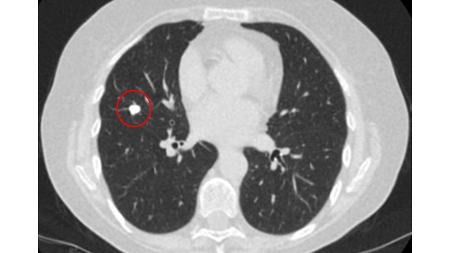

Padrão de calcificação

Um padrão denso de calcificação condroide, laminado e central (geralmente chamado de calcificação em pipoca) ou um padrão difuso de calcificação sugere fortemente que o nódulo seja benigno.[Figure caption and citation for the preceding image starts]: Tomografia computadorizada (TC) mostrando granuloma calcificado benigno no lobo médio direito, estável há >10 anos. O paciente relatou pneumonia prévia no mesmo ladoDo acervo de Dr. George Tsaknis, MD, PhD, FRCP (Londres), MRQA, MAcadMEd, PGCert; usado com permissão [Citation ends].

Uma razão de probabilidade calculada para malignidade com um padrão benigno de calcificação é próximo de zero.[19] Aproximadamente 10% dos nódulos malignos apresentam um padrão de calcificação não benigno (ver E e F).[26][Figure caption and citation for the preceding image starts]: A-D: padrões de calcificação de nódulos benignos; E, F: podem ser vistos em nódulos malignosMazzone P.J., Stoller J.K. Semin Thorac Cardiovasc Surg. 2002;14:250-260; usado com permissão [Citation ends].